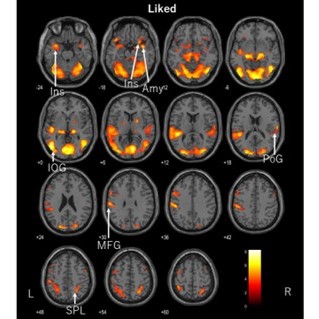

ASMR(autonomous sensory meridian response)は、若者の間で人気が高まりYouTubeなどで動画再生回数が伸びています。ASMRでリラクゼーション効果が得られる報告は多くありますが、種類が多岐にわたり個人の好みが偏っています。我々はこの個人差に着目し、個人の好みに合ったASMR動画がもたらすリラクゼーション効果の神経科学的根拠を解明しました。課題遂行中の脳機能を機能的MRIの手法で撮像を行いました。解析の結果、好きなASMRを視聴したときだけ扁桃体と中前頭回、左右島皮質の脳内活性化部位が特定されました。これらの部位は、大脳辺縁系ドーパミン回路への関与と自律神経バランスが整ったと考えられます。このことは、個人の好みに合ったASMRを利用することがより効果的であり、ポジティブな気分を得られることが明らかとなりました。今後は、不安およびうつ病患者の治療として利用される可能性が示唆される。

2、コントロールと好きなASMRと好きでないASMRを課題とし機能的MRIを撮像し解析した結果、好きなASMRの課題の時だけ、両側島皮質や扁桃体、中前頭回で活性化がみられました。